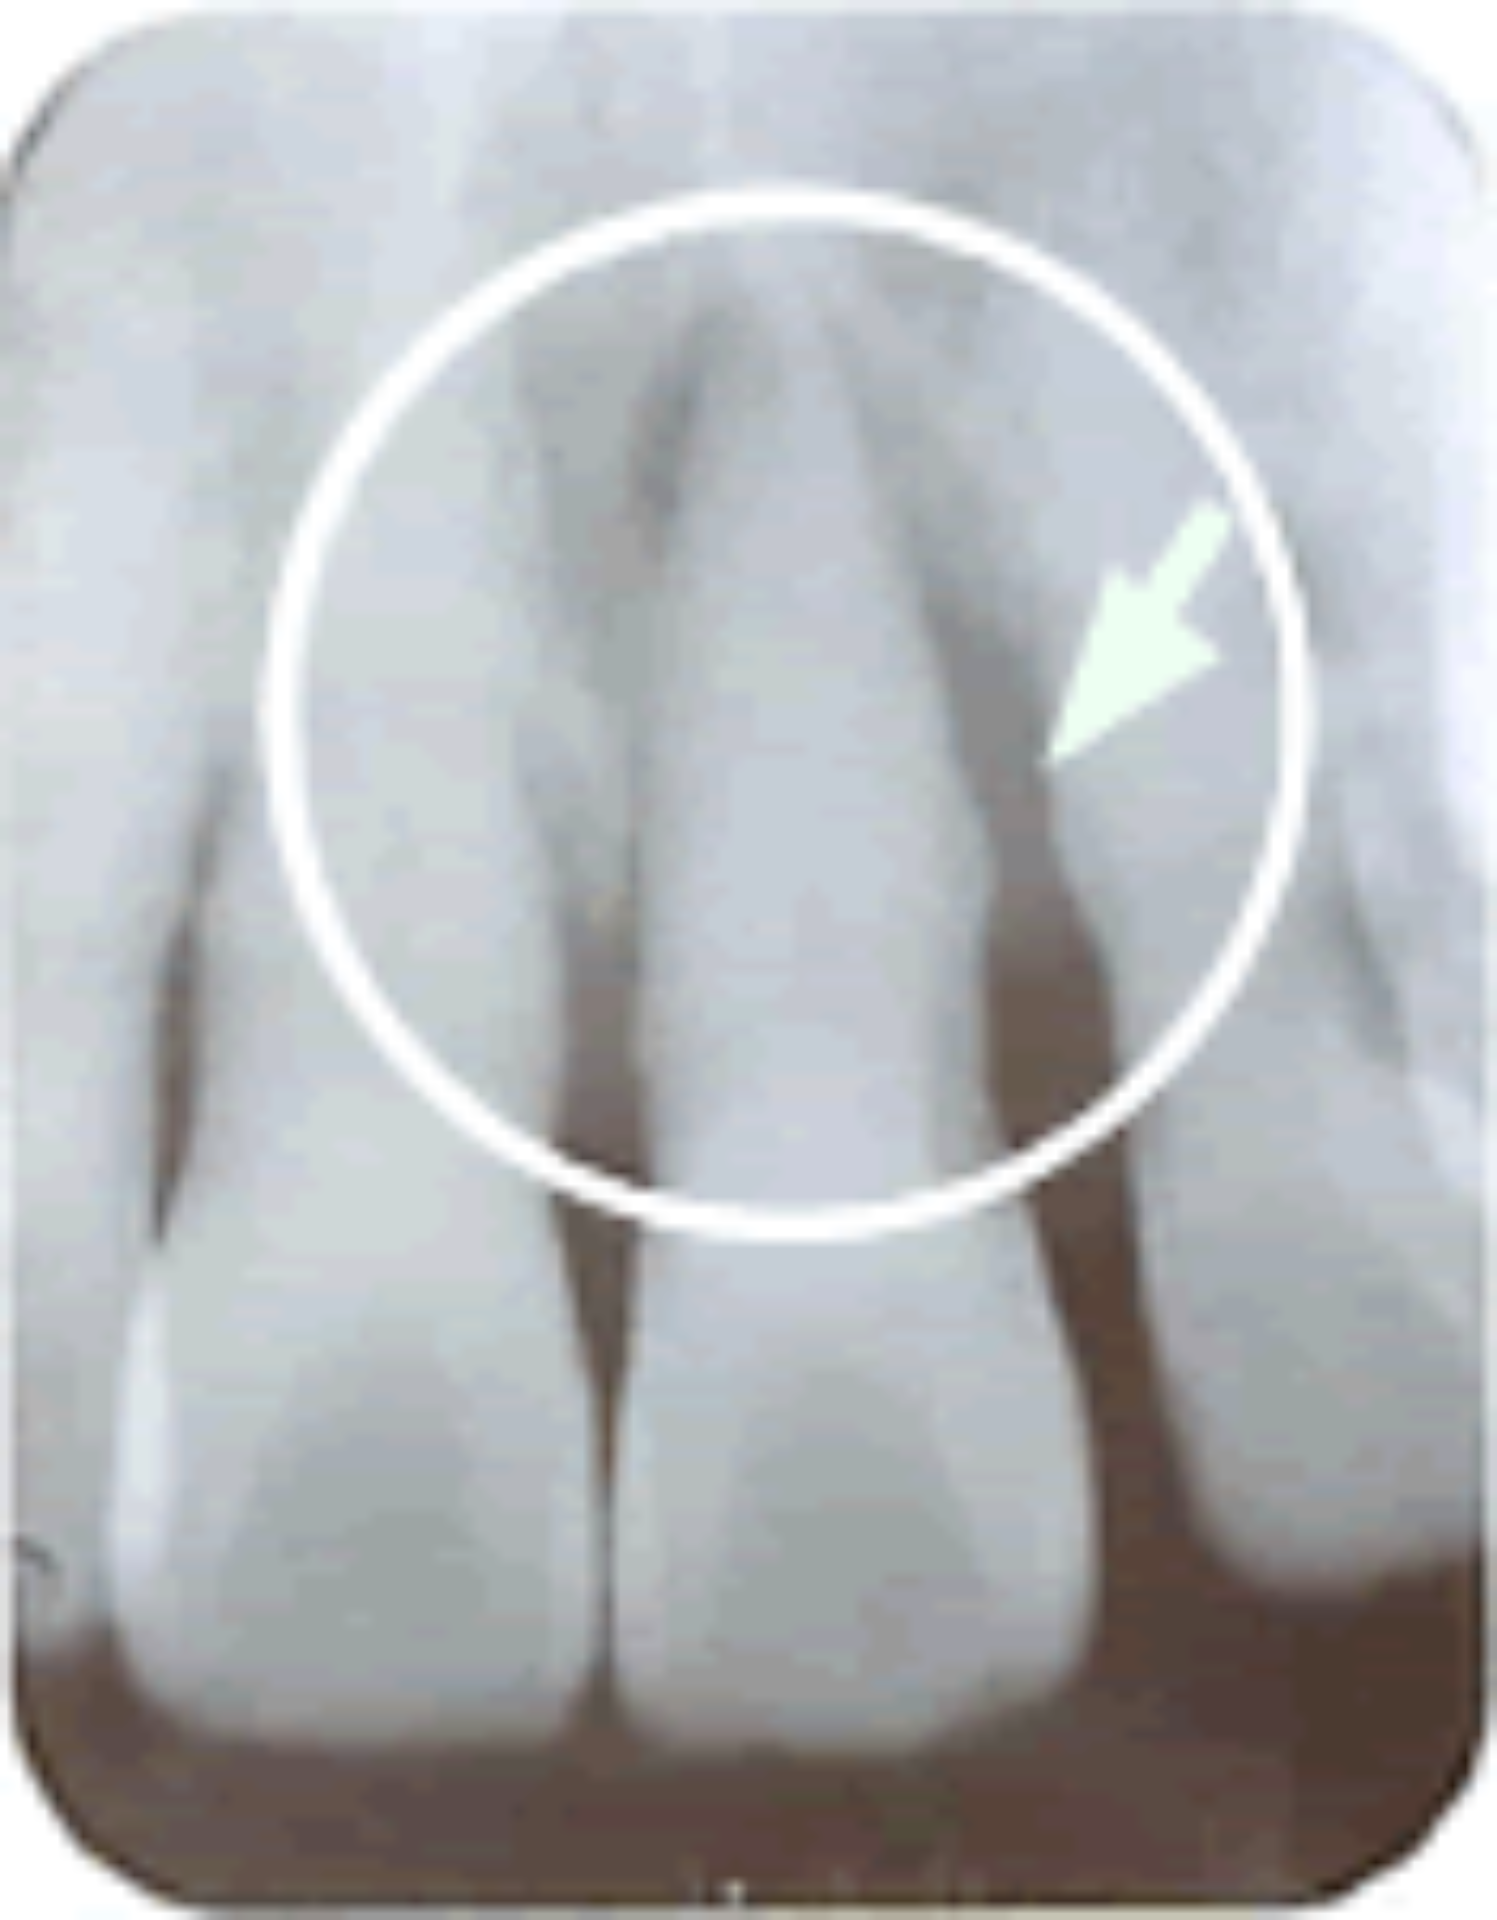

正常な歯周組織の 正常な歯周組織のX線写真 |

ブラキシズムによって歯周病が悪化している歯のX線写真。 ブラキシズムによって歯周病が悪化している歯のX線写真。 矢印は骨が吸収したところ |